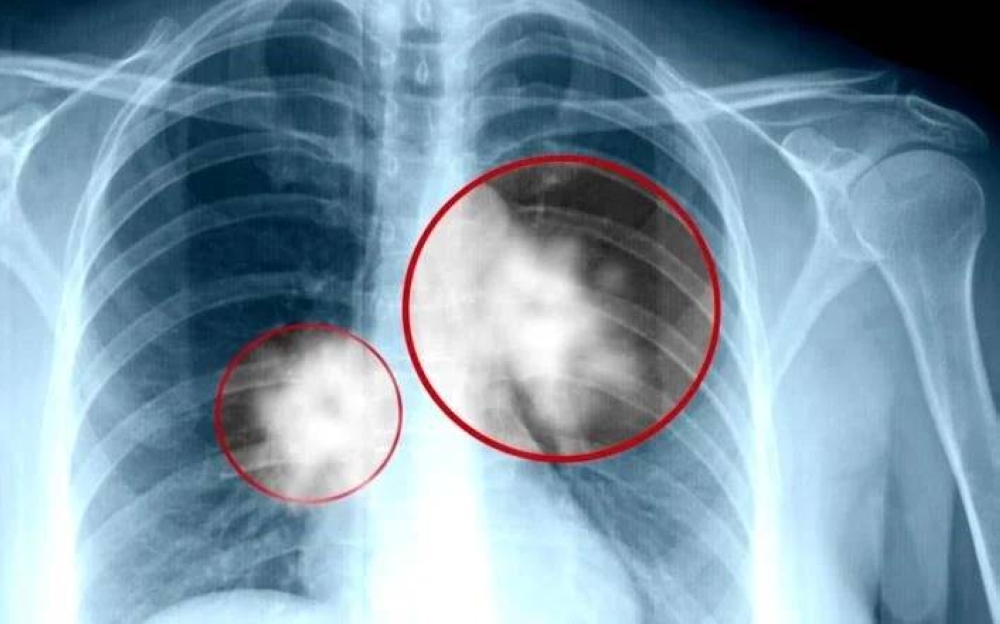

ويُشكل سرطان الرئة ذو الخلايا غير الصغيرة نحو 85% من إجمالي حالات سرطان الرئة، وهو السبب الرئيسي للوفيات المرتبطة بالسرطان عالمياً، وينقسم NSCLC إلى 3 أنواع رئيسية: الأدينوكارسينوما (الأكثر شيوعاً)، وسرطان الخلايا الحرشفية، وسرطان الخلايا الكبيرة. ويُصنف NSCLC المتقدم على أنه سرطان انتشر إلى أجزاء قريبة من الرئتين (محلي متقدم) أو إلى أعضاء أخرى (نقيلي)، ما يجعل العلاج أكثر تعقيداً ويقلل من فرص الشفاء.

ويُصيب سرطان الرئة ملايين الأشخاص سنوياً، ويُعد تحدياً صحياً عالمياً بسبب ارتباطه الوثيق بالتدخين، إضافة إلى عوامل أخرى مثل التلوث البيئي. ويُعاني المرضى في المراحل المتقدمة من أعراض شديدة، مثل: السعال المزمن، ضيق التنفس، وفقدان الوزن، ما يؤثر على جودة حياتهم.

Non-small cell lung cancer accounts for approximately 85% of all lung cancer cases and is the leading cause of cancer-related deaths worldwide. NSCLC is divided into three main types: adenocarcinoma (the most common), squamous cell carcinoma, and large cell carcinoma. Advanced NSCLC is classified as cancer that has spread to nearby parts of the lungs (locally advanced) or to other organs (metastatic), making treatment more complex and reducing chances of recovery.

Lung cancer affects millions of people annually and poses a global health challenge due to its close association with smoking, along with other factors such as environmental pollution. Patients in advanced stages suffer from severe symptoms, such as chronic cough, shortness of breath, and weight loss, which significantly impact their quality of life.